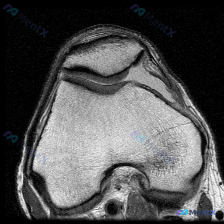

拿到这份踝关节冠状位T2序列MRI,一开始问题问的是有没有软骨异常,我整理了完整读片和分析思路,大家一起看看。 一、先看影像基本信息 这是踝关节冠状位T2加权MRI,我们逐层梳理所有结构的表现: 1. 骨性结构:胫骨、腓骨远端和距骨形态完整,没有明显骨折线,骨髓信号整体尚可,但距骨内部和踝关节周围部...